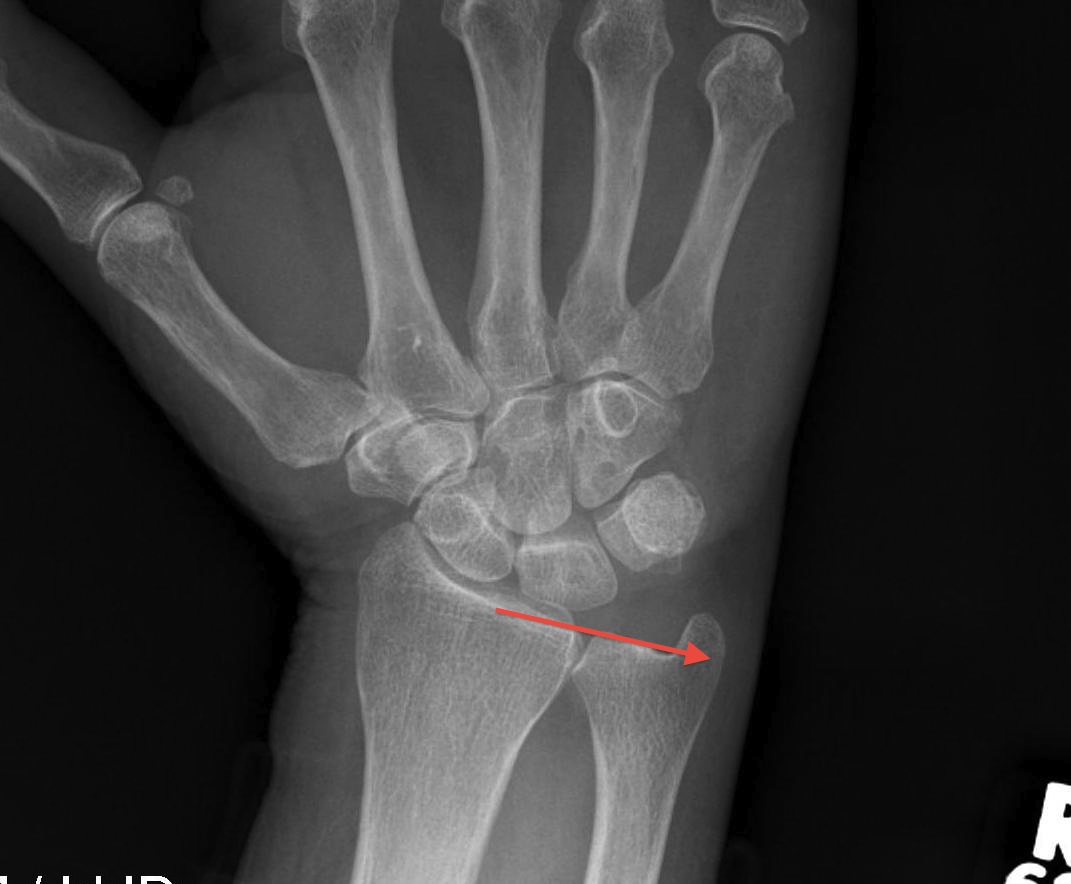

Ulna variance

Supination and pronation alter variance

- varies up to 3 mm with wrist position

- pronation increases ulnar variance

- supination decreases variance

90 / 90 view

- zero rotation view

- neutral supination / pronation

- PA film with wrist in neutral

- elbow 90° / shoulder abducted 90°

Line from lunate fossa and ulna head

- wide variation in population

- mean ulna variance is 1 mm (range 2 - 4)

Ulna neutral

Ulna positive

Ulna negative